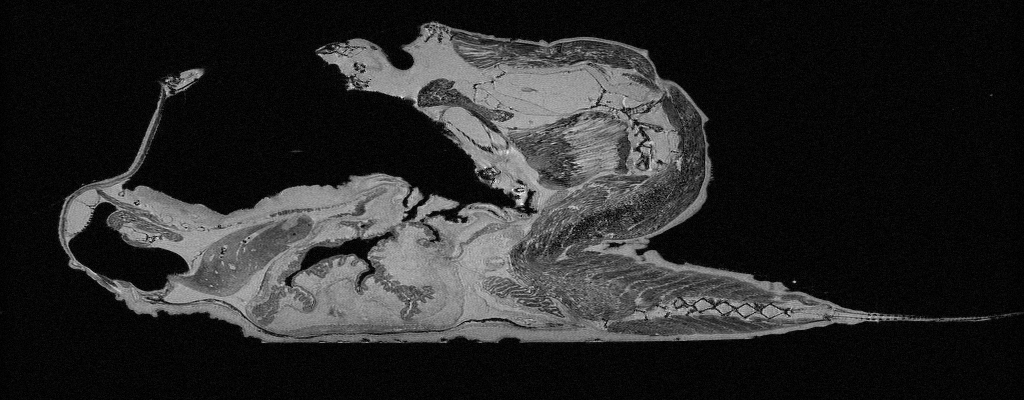

Click image to view full size.